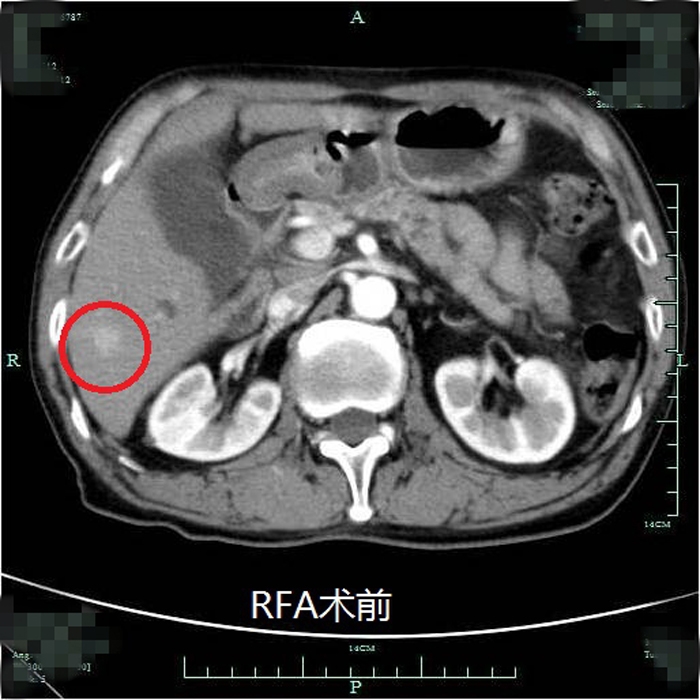

典型射頻治療患者術(shù)前術(shù)后效果對比(非該尾狀葉患者)

??? 近年來,我院肝膽外科在肝癌治療的綜合體系方面更加合理完善,肝癌射頻消融術(shù)已逐步成為繼肝癌切除術(shù)、經(jīng)皮選擇性肝動脈栓塞化療(TACE)后常規(guī)開展的治療手段。自2012年開展此項技術(shù)以來,針對常規(guī)部位的肝癌射頻消融均取得了非常理想的效果。但由于尾狀葉腫瘤位置較深,周圍大血管包繞,不僅手術(shù)難度大,能否安全徹底地對該部位腫瘤進行射頻消融也具有一定的挑戰(zhàn)性。此次在超聲影像等多學科的團隊協(xié)作下,成功完成了尾狀葉腫瘤的射頻消融術(shù)。